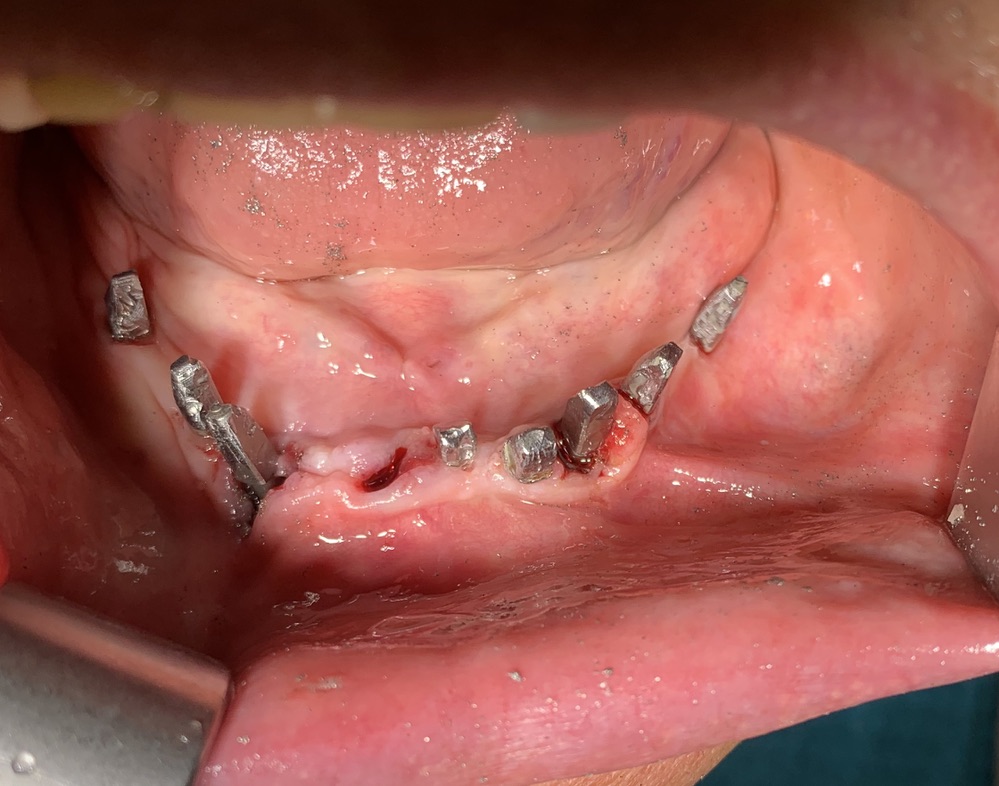

Acquafredda Clinic Age 70 years

Date and number of interventions already made: before 2008 2 Implants. 10/2008: 1 implant in 12. 07/2009: 2 implants in 21 and 11. 11/2009: 4 implants in 23,24,25,26. 05/2010: 1 implant in 22. 07/2010: 2 implants in 14.14. 08/2012: 2 Implants in 31.32. 05/2019: 2 implants in 34.36.

Date 10/07/2020

surname and name Xxxxxxx Xxxxxx

N ° existing implants 6 lower and 10 upper

Type of implant: Tramonte

N ° implants inserted: 2

Welding No

Dental area 33.43

Vixwin Acquafredda intraoral Rx app

CT scan yes

Extractive situation: immediate post-extraction implants

Density according to Misch: D2

Antagonist of natural fixed elements, implants or mobile prostheses: bridges on implants.

As shown in the extract from the chronological registry of implants shown above, the patient underwent several times to implant operations, facing sectoral problems as they arose.

All the implants have always coexisted with natural elements that presented variable patterns of periodontal disease.

In my opinion it is a remarkable situation if we compare it with the statistics reported by the official 'osseointegrated' implantology. I’ve found it in many other patients with implant cases that coexist with natural periodontal disease elements without being affected by infections.

I attribute this happy condition to the particular shape in the emergency area of ​​the Tramonte implants. They are equipped with a long thin neck. This guarantees the presence of a very tight adherent gingiva sleeve, effectively inhibiting the penetration of bacteria.

Furthermore, since it is not built in several parts (because it is a monobloc) ,it does not have internal cavities which when colonized by bacteria constitute very effective reservoirs in perpetuating an infectious and inflammatory condition.